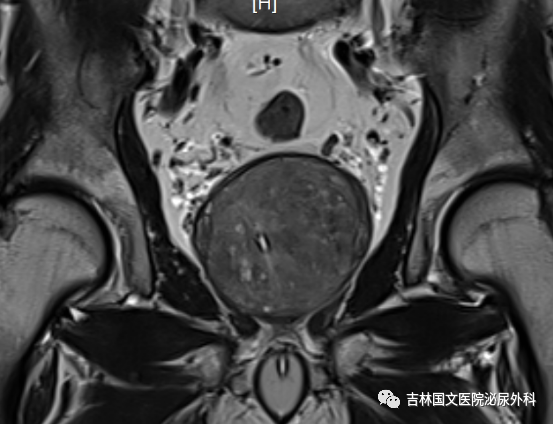

入院后行相關(guān)檢查,發(fā)現(xiàn)患者前列腺增生巨大,因治療延誤,已導(dǎo)致前列腺并發(fā)癥,出現(xiàn)膀胱功能受損,雙腎輕度積水。同時(shí)發(fā)現(xiàn)有腦梗死、雙肺支氣管炎、肺氣腫等基礎(chǔ)疾病,請(qǐng)相關(guān)科室會(huì)診,積極調(diào)整,改善身體素質(zhì)。同時(shí)明確向家屬告知手術(shù)風(fēng)險(xiǎn),手術(shù)后果,取得家屬支持認(rèn)可。家屬全力配合。經(jīng)認(rèn)真準(zhǔn)備,

患者在椎管內(nèi)麻醉下行經(jīng)尿道前列腺電切術(shù)。術(shù)中見(jiàn)前列腺中葉側(cè)葉明顯增大,向膀胱突出,尿道前列腺部明顯延長(zhǎng),因前列腺阻擋,膀胱加強(qiáng)收縮,膀胱壁明顯增厚,形成特有“小房小梁”結(jié)構(gòu)。在麻醉科精心配合下,谷欣權(quán)教授、張寶主任給予認(rèn)真細(xì)致手術(shù),術(shù)中反復(fù)止血,術(shù)后出血少,未輸血。術(shù)后認(rèn)真看護(hù),未出現(xiàn)腦梗死肢體功能障礙,未出現(xiàn)呼吸功能衰竭、心功能不全等常見(jiàn)并發(fā)癥。拔出尿管,患者排尿通暢,如開(kāi)閘洪水,一瀉千里,老人露出久違笑容,家屬也非常開(kāi)心,壓在心中的石頭終于落了地。